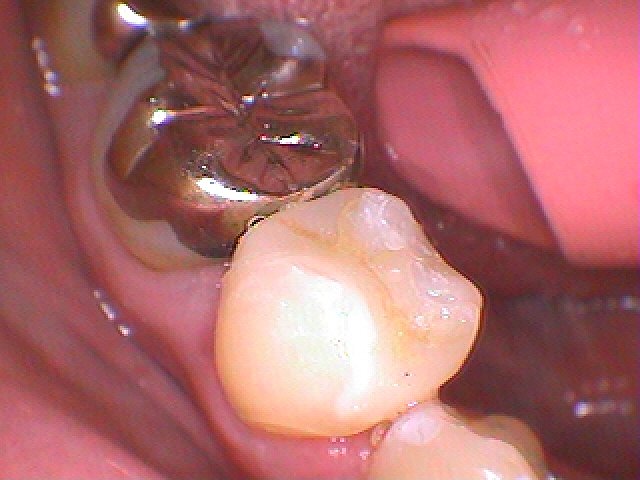

本来の歯のようにきれいに仕上がりました

セレックセラミックにて修復しています

綺麗に仕上がりました